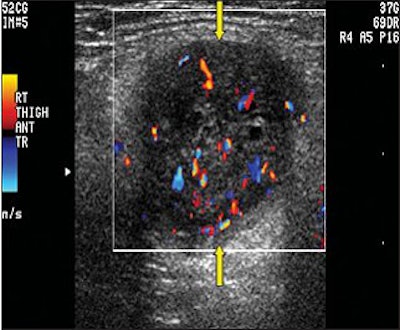

| Schwannoma in a 75-year-old man. Above, color Doppler ultrasonography of the lower anterior leg shows a well-defined oval mass (arrows) with peripheral and central color flow signals, suggesting a hypervascular tumor. Below, neurofibroma in an 84-year-old man. Color Doppler ultrasonography of the right thigh shows a well-defined mass (arrows) with peripheral and central hypervascularity. |

Overall, ultrasound exams did not lead to statistically significant results for making the differential diagnosis, the authors stated. The internal echogenicity was hypoechoic in 100% of the schwannomas and 100% also showed posterior acoustic enhancement. Likewise, 96.2% of the neurofibromas were hypoechoic and 96.2% showed posterior acoustic enhancement. On color Doppler, all showed hypervascular changes. Additional results are shown below.

These results dovetailed with the traditionally held notion that ultrasonography cannot distinguish between the two entities because both are "well-defined solid hypoechoic soft-tissue masses with posterior acoustic enhancement," the authors wrote (Journal of Ultrasound in Medicine, February 2008, Vol. 27:2, pp. 161-166).